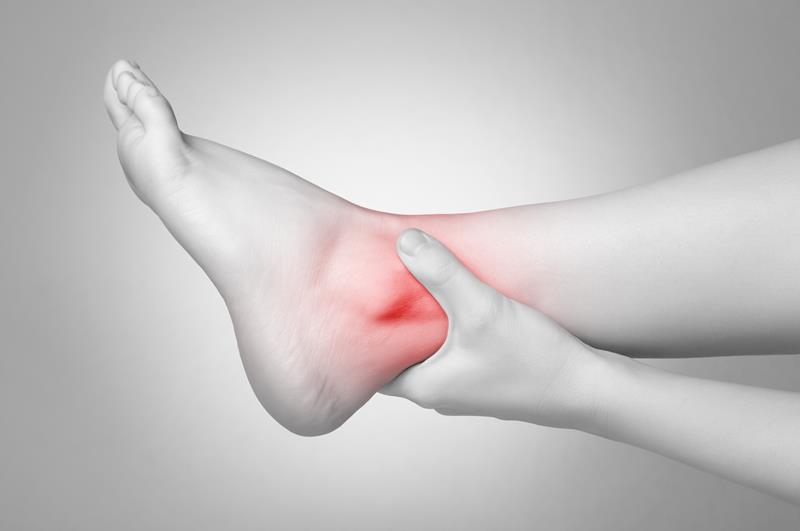

- Achilles Pain